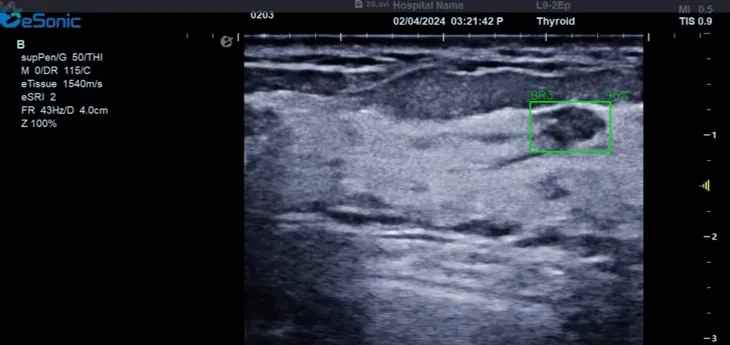

银河官网医疗(ESI)表示,其最新的人工智能功能可以帮助到医疗机构的工作效率,功能包括,实时、动态、快速自动识别病灶,良恶性病灶概率预测,甲状腺结节和乳腺的二维灰阶动态自动实时检测需求,提供多个结节动态检测轮廓框。实时获取多幅具备临床特征(大小、属性等)的结节切面,同时提供当前切面所示结节的结节大小、属性特征、TI-RADS 分级。

对于甲状腺结节相关的自动检测功能,甲状腺结节病灶检出率≥95%,良恶性分类灵敏度≥90%、良恶性分类特异度≥85%。